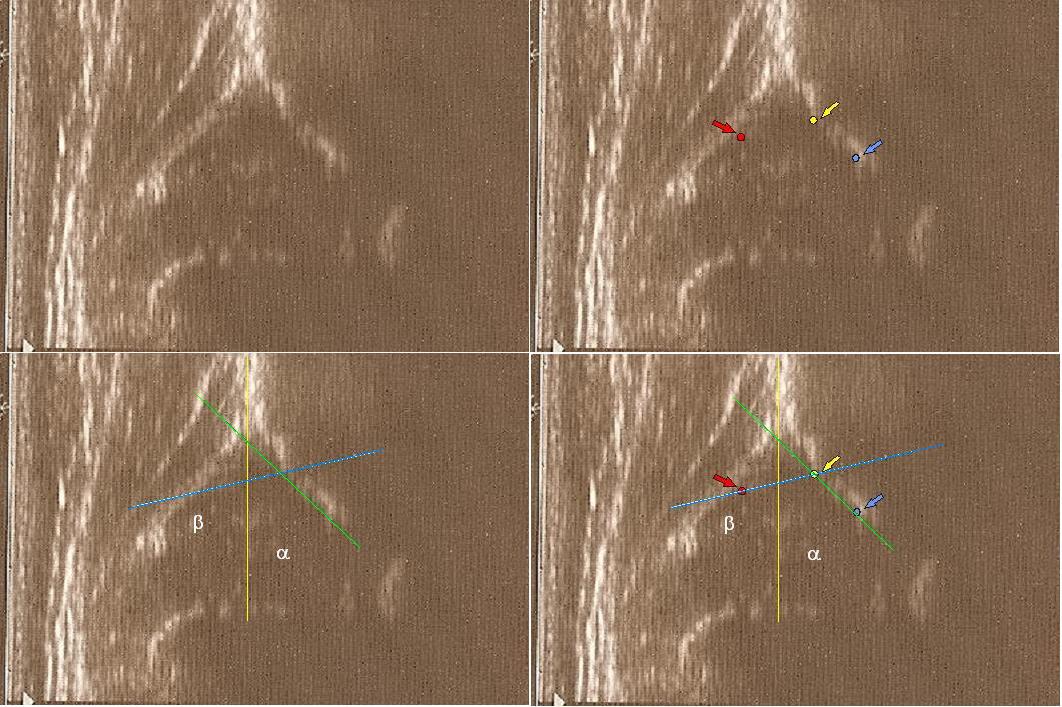

powyżej staw prawidłowy Typ I dach kostny dobry;brzeg kostny tępy ;dach chrzestny pokrywa

dolne zdjęcia

strzałki pokazują obrabek(czerwona):brzeg kostny (żółta);gałąż dolna(niebieska) ,

prawidłowy przebieg linii dachu kostnego(niebieska) stycznie do echa gałęzie dolnej i echa brzegu kostnego ;

linii dachu chrzęstnego (czerwona) stycznie do brzegu kostnego i przez środek geometryczny obrąbka i

linii podstawnej ( żółta

typ I czerwone kropki(od lewej) pokazują punkty do kreślenia 1 środek geometryczny obrąbka 2.brzeg kostny;3.gałąż dolną kości biodrowej

Typ IIc czerwone kropki od lewej) pokazują punkty do kreślenia 1 środek geometryczny obrąbka 2.brzeg kostny(dwa punkty);3.gałąż dolną kości biodrowej